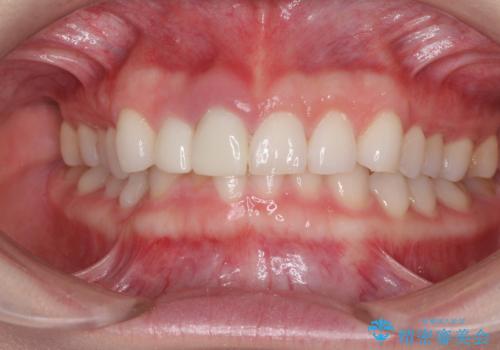

治療前、下顎前歯はほとんど見えない咬み合わせでしたが、矯正治療によりディープバイトが改善されました。

矯正治療中に前歯2本のクラウンは外れてしまい、途中仮歯に替える必要があったので期間は掛かりましたが、歯列も整い、負担のかからない咬み合わせを達成することができました。